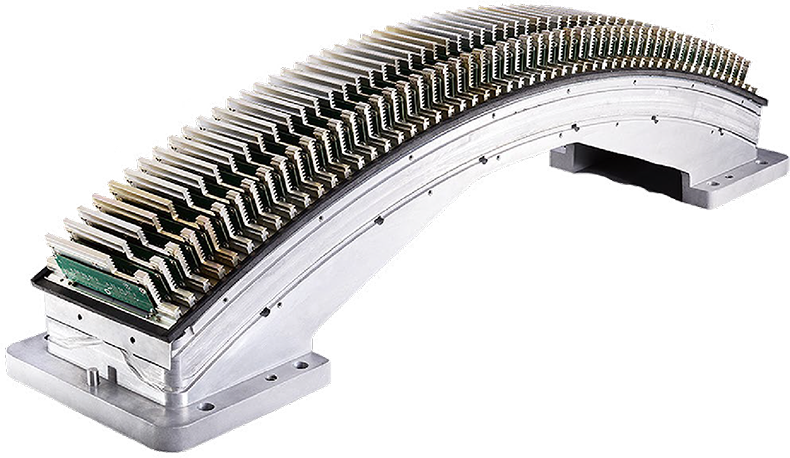

Новое поколение керамических детекторов Vision HD Detector

В компьютерных томографах Insitum используются твердотельные детекторы нового поколения из оксисульфида гадолиния. Применение в качестве матрицы соединений гадолония позволяет снизить лучевую нагрузку и уменьшить концентрацию контрастного вещества без ущерба качеству изображения. Точность сканирования гарантируется такими свойствами керамики, как поглощение энергии в широком диапазоне, высокая чувствительность к затухающим излучениям, большой коэффициент сорбции рентгеновских лучей.

32-рядная детекторная решетка

32-рядная детекторная система, независимо разработанная компанией SinoVision, позволяет осуществлять непрерывный сбор перекрывающихся данных о каждой анатомической детали и получать данные диплоидного детектора, что позволяет избежать искажений мягких тканей и на границе раздела костной ткани и воздуха и добиться непревзойденного качества изображения. Новое поколение редкоземельных керамических детекторов может обеспечить сверхвысокую эффективность поглощения, сверхнизкий электронный шум и высокое качество изображения, точно воспроизводя каждое значение вокселя изображения и достигая высокого изотропного разрешения.

Настоящий 32-рядный физический детекторный модуль с воссозданием 32 изображений за один оборот. Качество изображения в формате Full HD, с высокой скоростью и тонким срезом.

Удвоенное качество с 32-срезным детектором

КТ Insitum 32 использует физический 32-рядный равнопиксельный трехмерный детектор. По сравнению с традиционным 16-срезным КТ, он может выполнять обследование за то же время и при том же расходе энергии. Сверхвысокая изотропия достигается за счет оптимизированного размера кубических пикселей - 0,625 мм, который гарантирует, что изображения не будут искажаться при наблюдении под любым углом.

Конструкция равноудаленного детектора размером 32x0,625 мм в сочетании с получением и реконструкцией данных в режиме реального времени с помощью двухканального DAS и технологии переключения рентгеновских трубок позволяют получить действительно высокое разрешение, тонкий срез и быстрое сканирование.